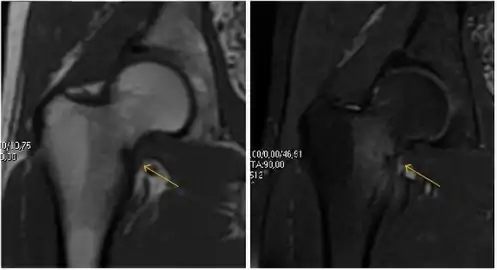

MRI has been shown to have 100% sensitivity and specificity in prospective studies of occult hip fractures. These fractures were diagnosed by bone marrow edema and a low signal fracture line, mainly on T1 or T2 weighted images (Figure 10).[1]

Figure 10:

Stress femoral neck fracture in a young athlete barely visible in X-ray film as a sclerotic line (arrow)[1]

In this case, Tc 99 scintigraphy shows a band of uptake[1]

Furthermore, T1 (left) and DP fat saturated (right) weighted MR images showed the fracture line and a pattern of edema.[1]